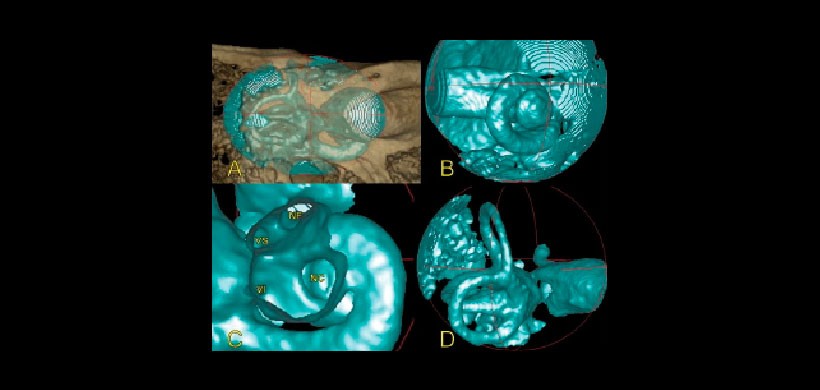

Figura 3: Reconstrucción volumétrica 3D con algoritmo de partes blandas. A: oído interno. B: cóclea. C: CAI (VS: vestibular superior; NF: nervio facial; VI: vestibular inferior; NC: nervio coclear). D: canales semicirculares.